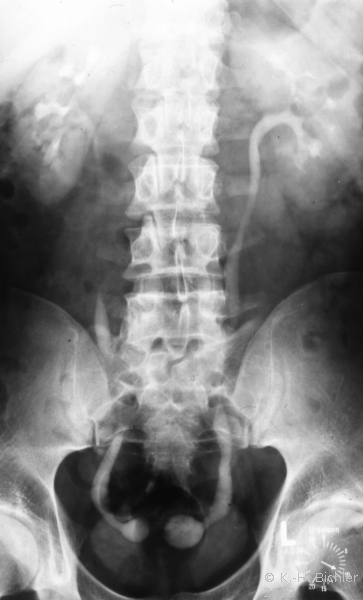

Das Ausscheidungsurogramm tritt bei Kindern und Jugendlichen wegen der relativ hohen Strahlenbelastung als kontrastmittelunterstützte radiologische Untersuchung gegenüber den nichtradiologischen Verfahren in den Hintergrund (eingeschränkte Indikation). Das gilt vor allem für junge Säuglinge, bei denen wegen deren noch schwächeren tubulären Nierenfunktion die Kontrastierung des Urogenitaltraktes nicht ausreicht. Es ist schon gar nicht als Untersuchungsmethode in Standardtechnik zu verantworten. Nach Überprüfung der gesetzlich vorgeschriebenen rechtfertigenden Indikation muss der Untersuchungsablauf fachkundig unter ärztlicher Aufsicht und an die Fragestellung angepasst nach Auswertung der jeweiligen vorausgegangenen Aufnahmen durchgeführt werden.

Literatur:http://www.bundesaerztekammer.de/page.asp?his=1.120.121.1042.5974; Leitlinie zur Qualitätssicherung in der Röntgendiagnostik: Qualitätskriterien röntgendiagnostischer Untersuchungen; Bundesärztekammer Stand: 23.11.2007. Sie schreibt das Verwenden von umschließenden Hodenkapseln, Ovarienabdeckungen und Bleigummiabdeckungen für den an das Nutzstrahlenfeld angrenzenden Körperbereich vor (

10 Abbildungen).